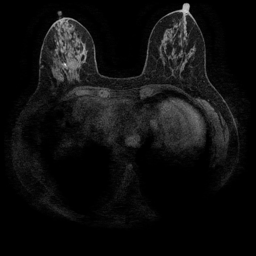

Magnetic field strength. 3T scanners offer higher magnetic field strength, improving signal-to-noise ratio (SNR) and image resolution for sharper, more detailed images [24]. However, they are more prone to artifacts, heating effects, and signal loss, especially around metal implants [5]. As such, our proposed dataset involving this spurious signal features a non-local spurious signal that influences the entire image rather than a localized region. An example set of images obtained from 1.5T and 3T devices are provided in Figure 3, showing that it is visually not possible to distinguish 1.5T MRIs from the 3T ones.

Vertical orientation. Different from magnetic field strength, which affects the entire image globally, vertical orientation is a local feature that only alters the spatial arrangement of structures within the image. This transformation does not modify the underlying tissue characteristics or signal properties but instead introduces artificial correlations that models may exploit as shortcuts.